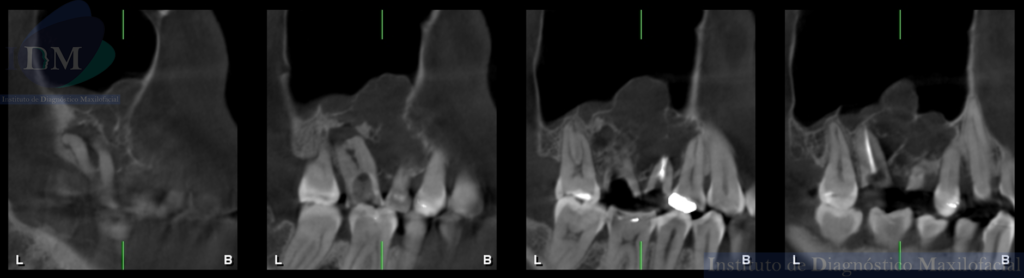

CORTES TANGENCIALES

Así mismo en la tomografía volumétrica de haz cónico se evidencia un borramiento parcial de laminas duras, de las piezas 14, 15 y 17. Presentando un tamaño aproximado de 21,20 mm x 21,40 mm x 13,26 mm e invadiendo parte del seno maxilar derecho.